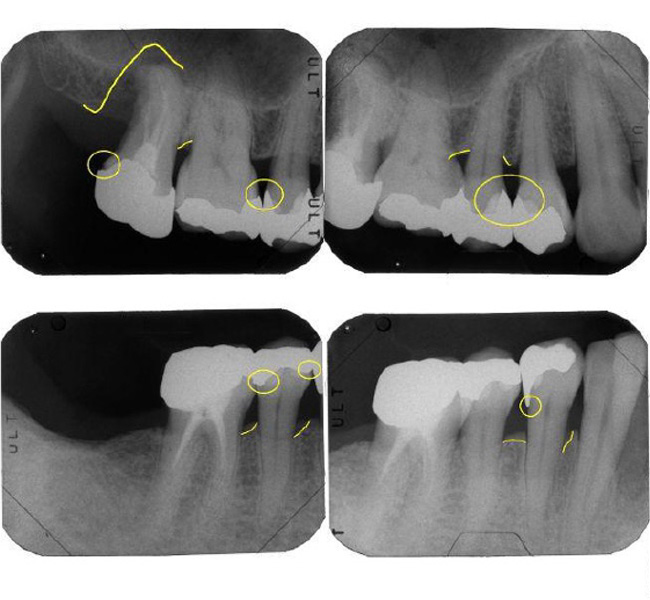

治療前

| 治療内容 | 全顎治療:歯周病治療、抜歯、根管治療、 咬合治療・矯正治療、フルメタルクラウン(保険) |